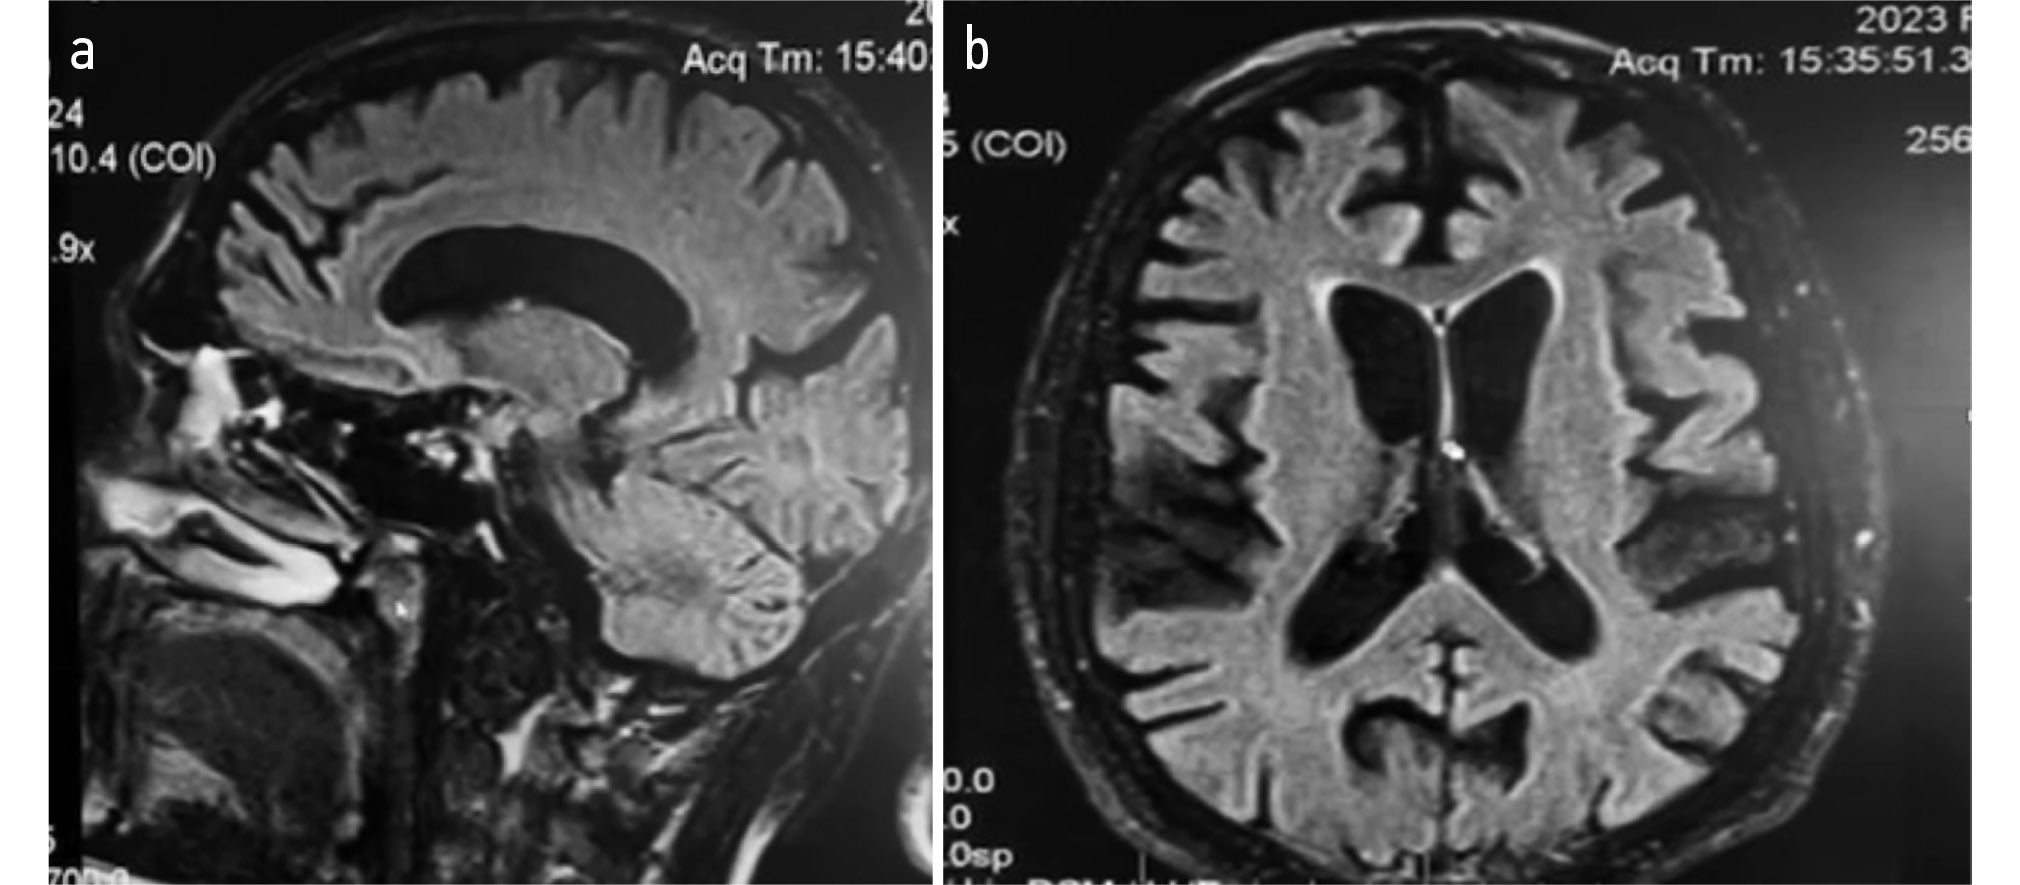

Магнитно-резонансная томография (МРТ) головного мозга (рис. 1): признаки выраженной атрофии головного мозга, преимущественно лобной и височной областей. Электронейромиография мышц верхних конечностей: проводящая функция моторных и сенсорных волокон нервов рук не нарушена. По результатам игольчатой миографии — признаков текущего денервационного поражения в руках и ногах нет. При тестировании мышечной силы — признаков мышечной слабости нет. Тесты на скрытую слабость — отрицательные. Заключение: данных за наличие болезни двигательного нейрона нет.

Рис. 1. Магнитно-резонансная томография головного мозга в сагиттальной плоскости (a) и аксиальной плоскости (b): признаки выраженной атрофии (преимущественно-лобной и височной).

Fig. 1. Magnetic resonance imaging of the brain in the sagittal plane (a) and axial plane (b): signs of marked atrophy (predominantly frontal and temporal).